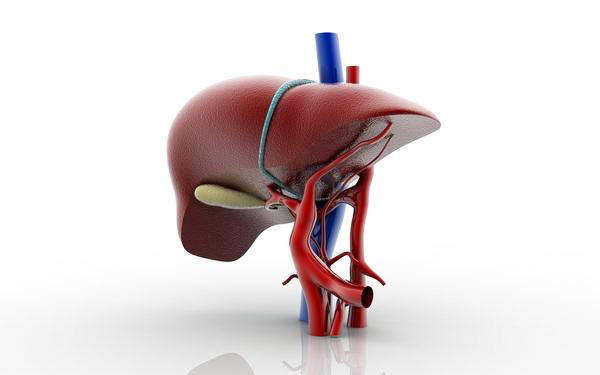

V lidovém léčitelství se dost často říká, že za různá onemocnění „můžou játra". Onemocnění očí, kůže atd. má spojitost s látkovou výměnou, přesněji řečeno s játry. Játra mají v lidském těle mnoho funkcí souvisejících s látkovou výměnou. Podílejí se na hospodaření se sacharidy (především glukózou), s tuky, tvoří cholesterol, hrají úlohu v metabolismu bílkovin a vitaminů. Tvoří se v nich žluč, dokážou zneškodňovat jedovaté látky, které se do těla dostávají zvenčí i které vznikají uvnitř těla při jeho práci a látkové přeměně. Mají dobrou schopnost regenerace. K projevům jaterních potíží patří únava, hubnutí, nevolnost, žloutenka, nervové a psychické změny, otoky, oběhové poruchy, hormonální změny, poruchy srážlivosti krve a selhávání ledvin.

V lidovém léčitelství se dost často říká, že za různá onemocnění „můžou játra". Onemocnění očí, kůže atd. má spojitost s látkovou výměnou, přesněji řečeno s játry. Játra mají v lidském těle mnoho funkcí souvisejících s látkovou výměnou. Podílejí se na hospodaření se sacharidy (především glukózou), s tuky, tvoří cholesterol, hrají úlohu v metabolismu bílkovin a vitaminů. Tvoří se v nich žluč, dokážou zneškodňovat jedovaté látky, které se do těla dostávají zvenčí i které vznikají uvnitř těla při jeho práci a látkové přeměně. Mají dobrou schopnost regenerace. K projevům jaterních potíží patří únava, hubnutí, nevolnost, žloutenka, nervové a psychické změny, otoky, oběhové poruchy, hormonální změny, poruchy srážlivosti krve a selhávání ledvin.